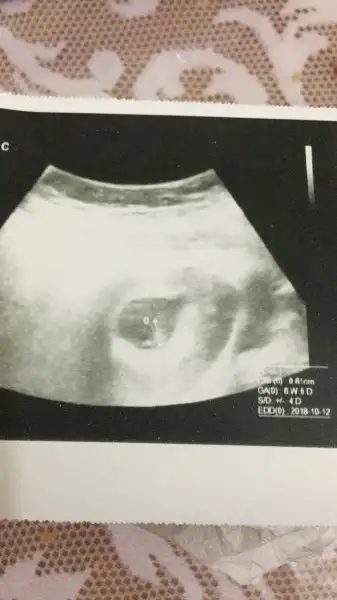

Kalp atısını duyamadm ama gordm bebegın kalbının attını hareket edıyodu 6+5 cıktı ultrason bes gun yanılabılır dedı dr kan ve ıdrar verdim vıtamınlere bakcakmıs ıkı haftaua gel dedı tekrar ılıskı uc aya kdr yasak nolur nolmaz dedı

9 gun once 6+1 dı 6+5 cıkması sacma oldu yanılma payıı barmıs devkete gıttım ultrasonda ses cıkmıyomus ama kalbının kasılıp attını gördm cok guzeldı yaramaza bak oturmus takılıyo kaynanama soyledm buarada esım ıstedı artık